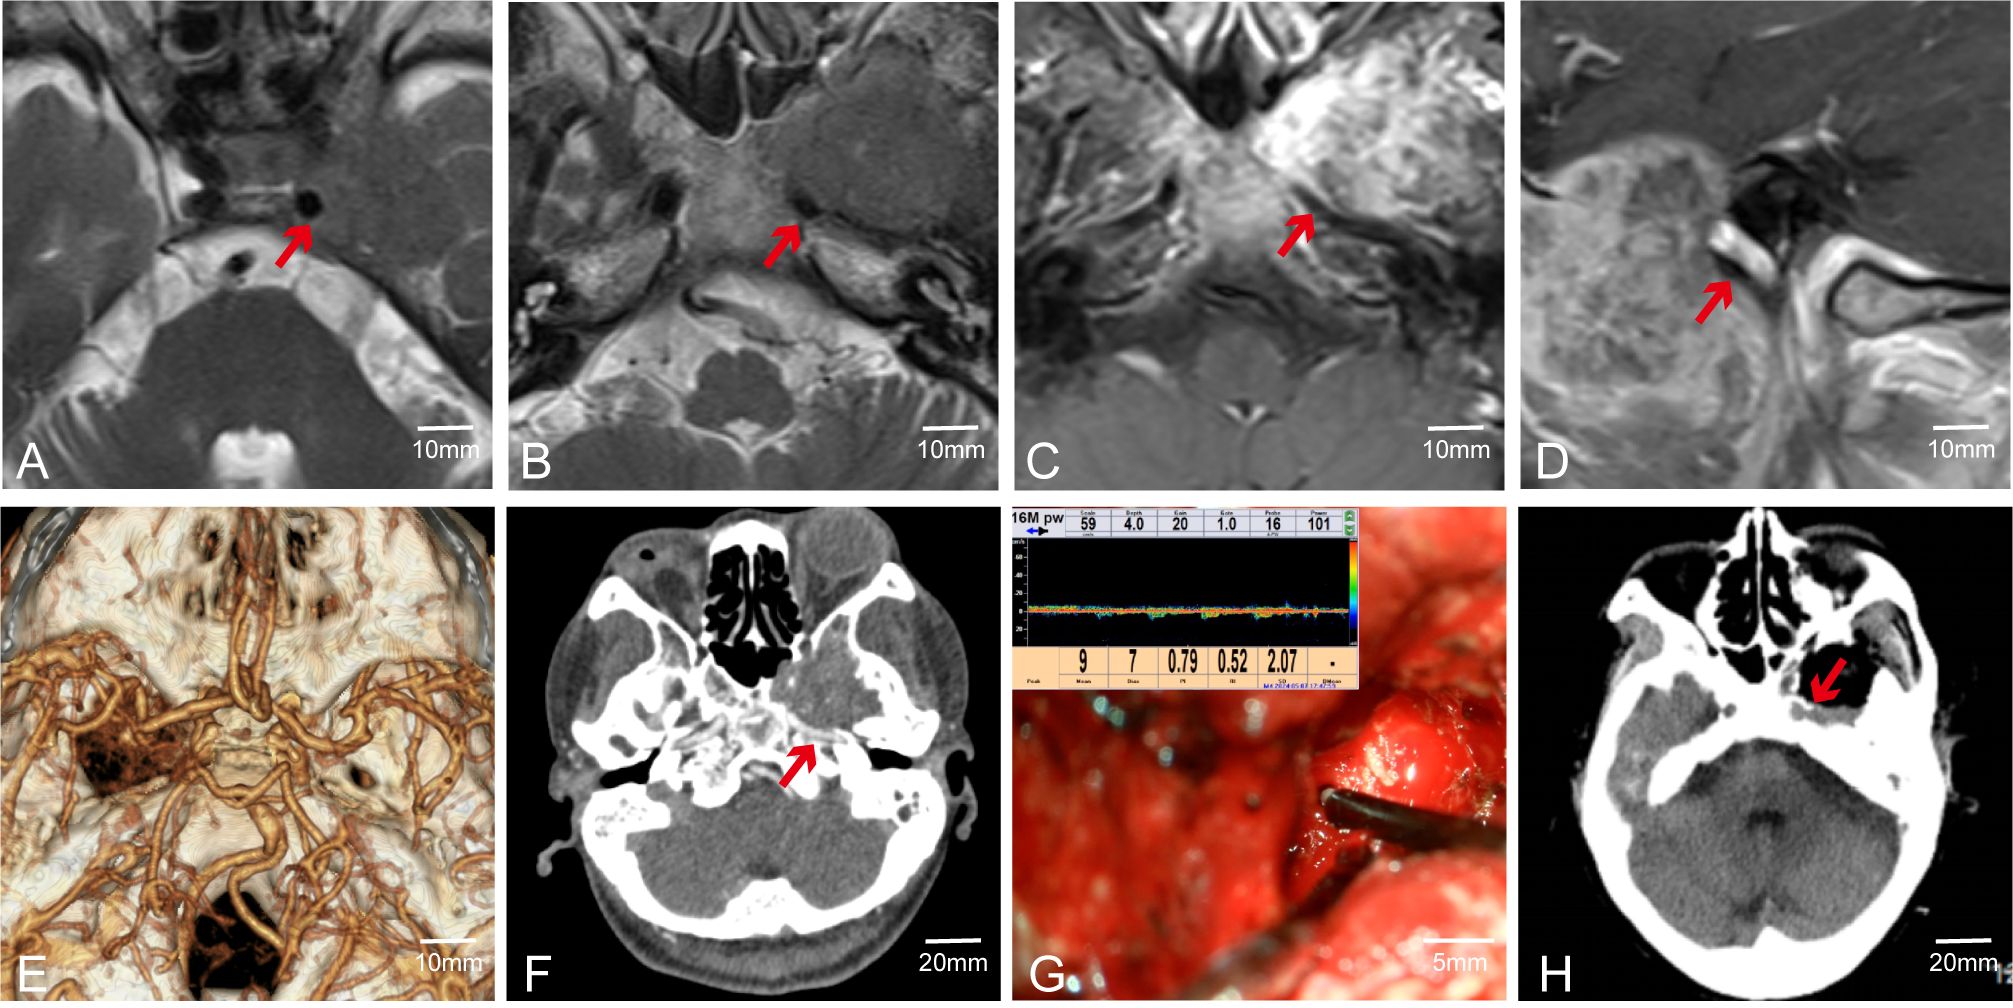

Although MVD can often assist surgeons in accurately locating major blood vessels during surgery, its effectiveness may be limited when there are structures such as bone or tumor capsules between the probe and the blood vessels. For instance, in Case 55, preoperative CTA was conducted to clarify the spatial adjacency and positional correlation between the tumor, surrounding major blood vessels, and skull base bone structures. Preoperative MRI indicated that the tumor was in close spatial proximity to the internal carotid artery; however, MRI could not adequately assess the integrity of the adjacent bone structures (Figures 6A–D). Preoperative CTA suggested the tumor involved the ICA segment at the foramen lacerum and the terminal segment of the petrous bone (Figures 6E, F). Post-complete tumor resection, MVD was used to detect the course of the ICA, but no ICA blood flow signal was detected around the tumor (Figure 6G). Postoperative CT indicated a thin layer of bone between the ICA and the tumor, with partial destruction of the ICA bony canal (Figure 6H). This demonstrates that MVD has weak tissue penetration, and when the probe is not in direct contact with the vessel wall, it may not be able to detect the vessel. In such cases, we rely on electrophysiological monitoring to ensure the blood vessels are not damaged.

Figure 6. Case 55. MVD combined with CTA was used to evaluate the vascular condition of patients. (A–D) Preoperative MR showed that the ICA was closely related to the tumor. (E, F) Preoperative CTA. (G) Intraoperative fail to detect internal carotid artery. (H) Postoperative CT showed ICA lateral has a thin layer of bone.